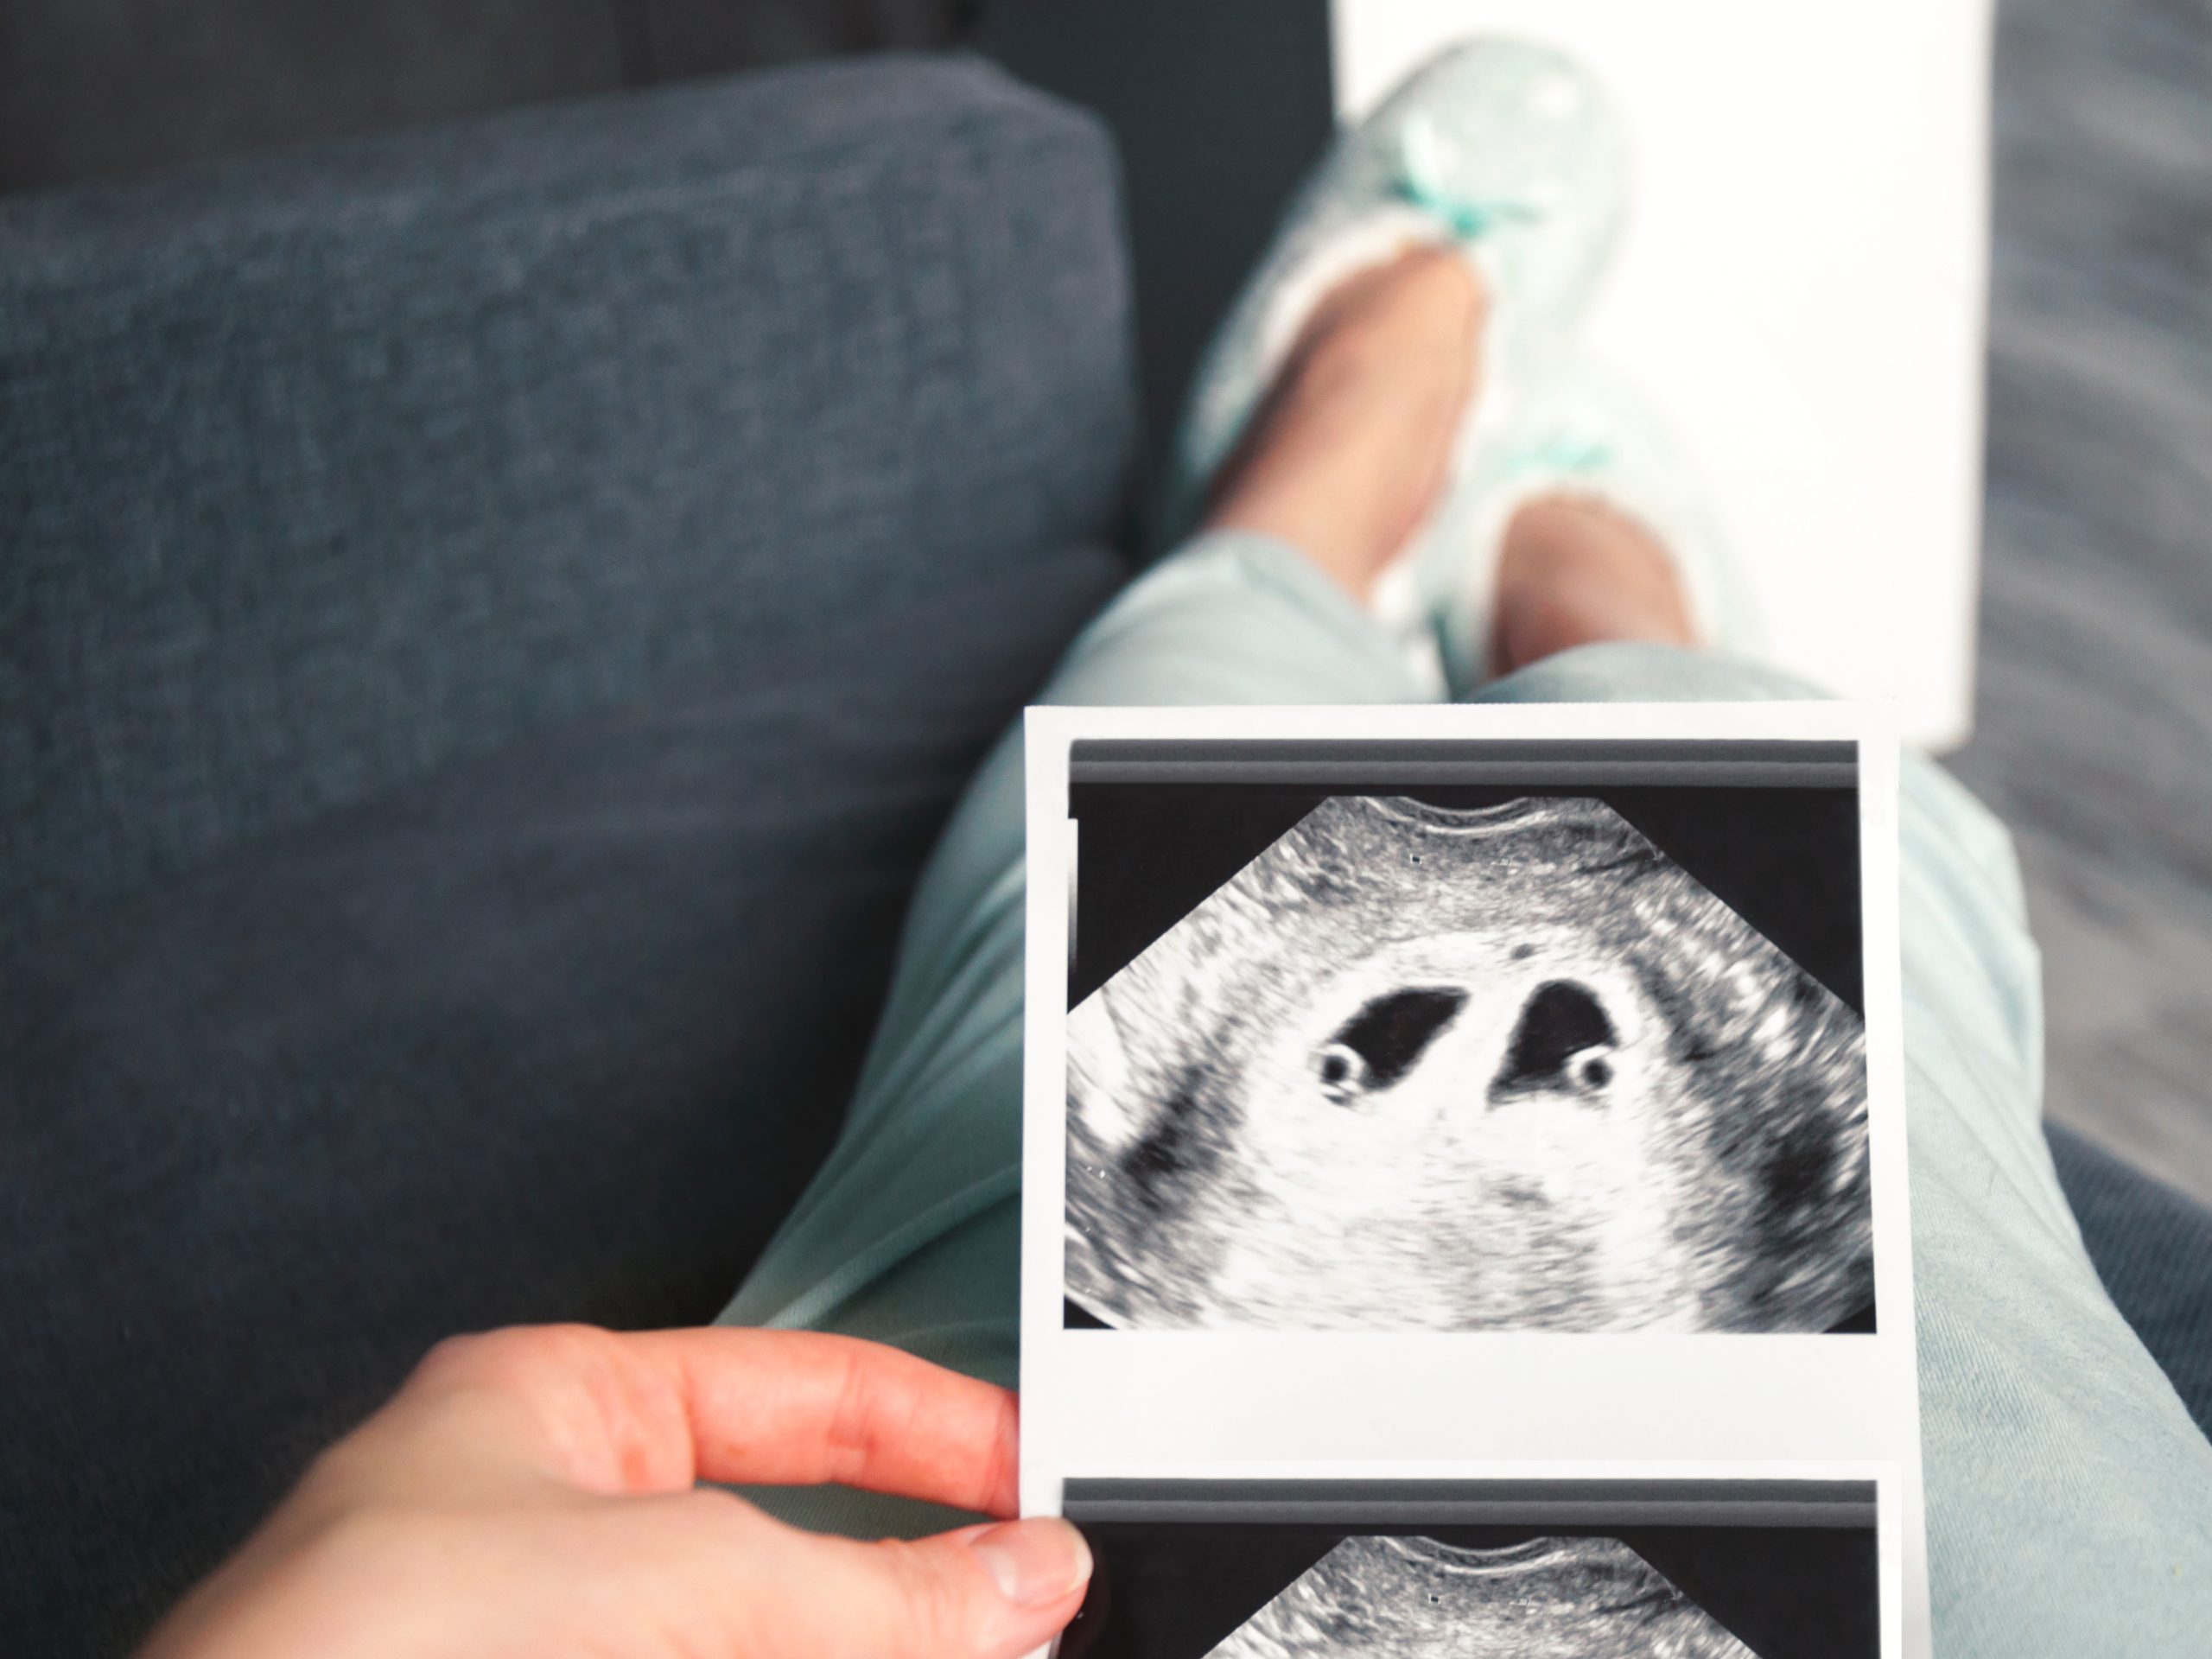

Ultrasonido de Embarazo 4D-HD Live(5D/6D)

¿Por qué conformarse sólo con un vídeo?

Con la más avanzada tecnología, claridad, velocidad y flexibilidad, en EcoQ te ofrecemos un ultrasonido 4D-HD Live (5D/6D) en nuestros consultorios de la CDMX para conocer a tu bebé.

- Ecografía 5D con imágenes en 3D de mayor resolución.

- Ecografía 5D HD con una mayor iluminación, nitidez y claridad para un aspecto más real del rostro de tu bebé.

Porque cada bebe es único. Ven a conocer a tu bebé por primera vez en EcoQ Ultrasonidos Quiñones, donde contamos con salas especiales para alojar a los familiares y proyectar en una pantalla de alta definición el desarrollo de tu bebé.